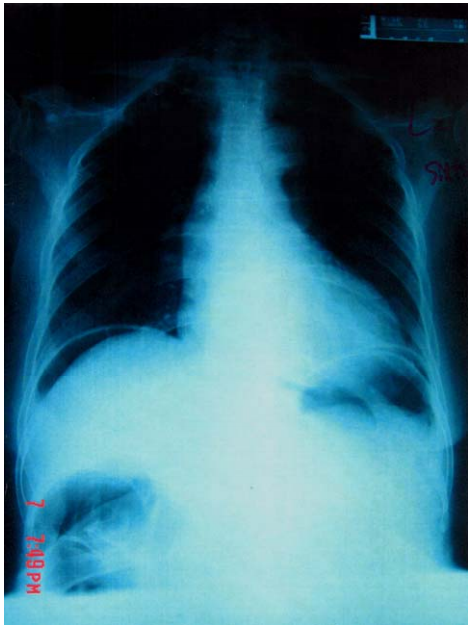

23 45 歲女性過去無開刀病史,最近一個月出現反覆性上腹痛,半夜突然發生上腹部劇痛,而至急診室 就診,理學檢查有腹膜炎徵象(peritoneal sign),WBC count為 12000/mm

3

,胸部X光如附圖,下列敘 述何者錯誤?

(A)初步診斷為 hollow organ perforation (B)若生命徵象穩定,保守性治療即可,不必開刀 (C)鼻胃管、點滴液、抗生素皆須給予 (D)消化性潰瘍(peptic ulcer disease)可能是其原因